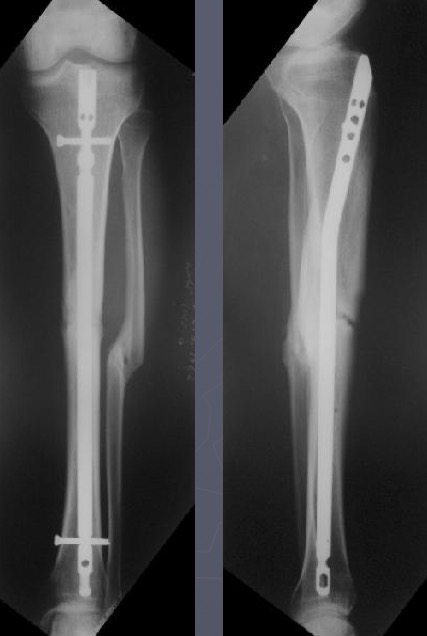

При интрамедуллярном остеосинтезе, конечно же, нужна максимальная конгруэнтность (параллельность) контактирующих поверхностей.

Совсем необязательно. Это при аппаратной фиксации, чтобы она не была бесконечной, надо обеспечить максимальную площадь контакта, или делать что-то дополнительное. Да и если фиксировать пластиной.

А когда в диафизе находится его эндопротез - достаточно сращения на ограниченном участке.

Это пример не про идентичный случай, а про категоричное утверждение, что "при интрамедуллярном остеосинтезе, конечно же, нужна...". Не нужна. Есть полный контакт - хорошо, нет - тоже не беда при интрамедуллярном остеосинтезе.

При аппаратном лечении - да, это проблема, когда срослось в виде песочных часов. И все время висит сакраментальный вопрос - уже можно снимать аппарат, или пусть еще походит?